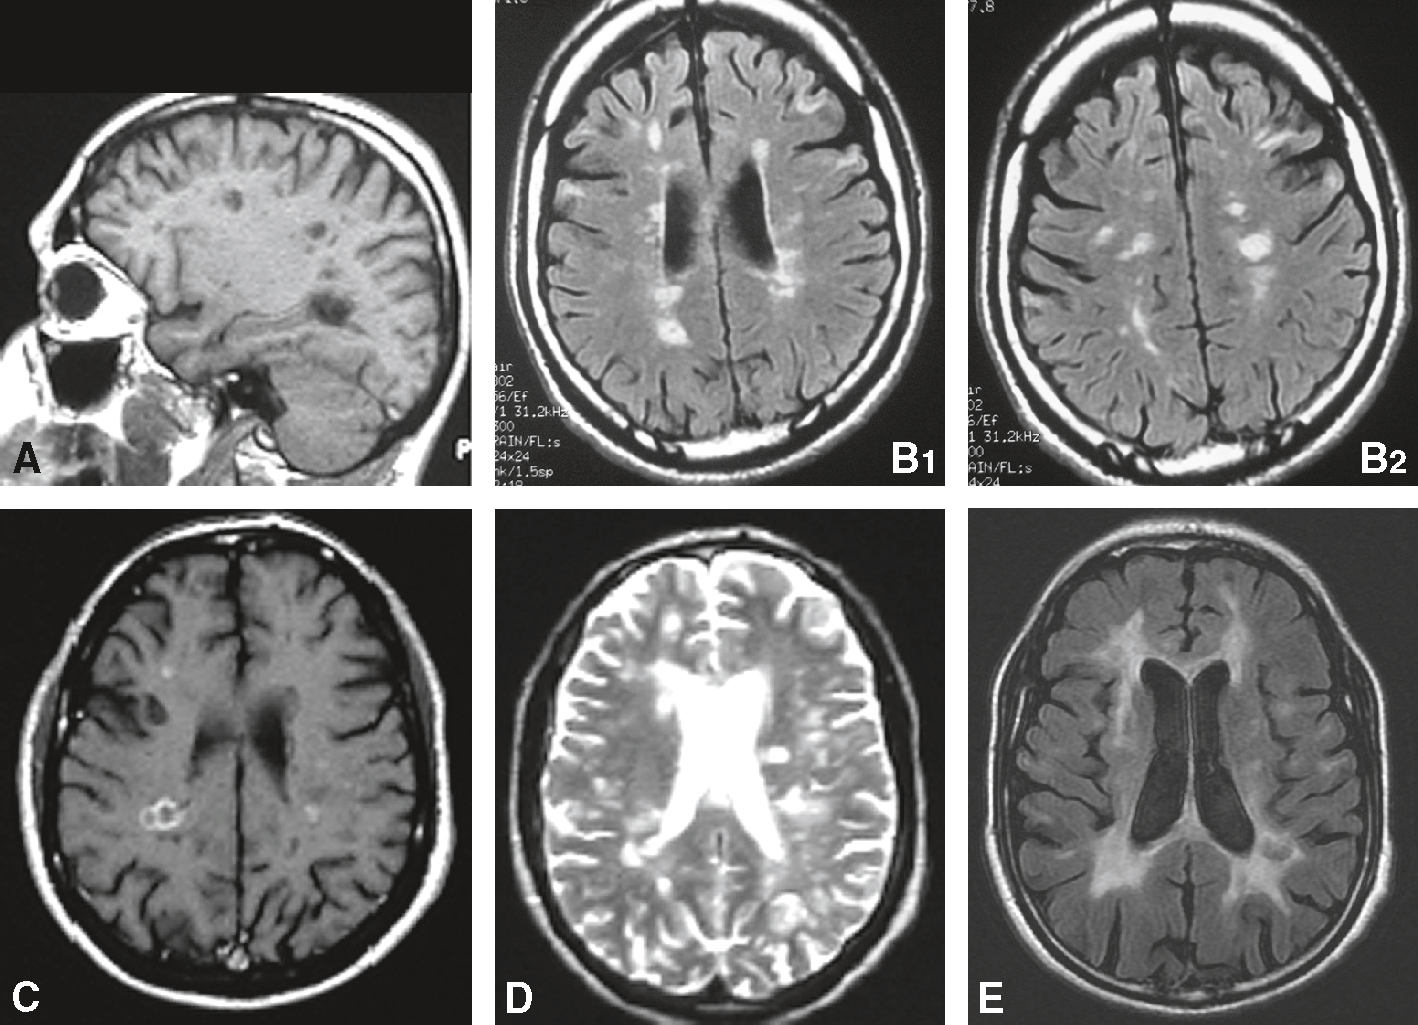

L’IRM encéphalique, éventuellement complétée par une IRM médullaire, est l’examen de choix pour le diagnostic de SEP (fig. 15.3 et 15.4). Les lésions apparaissent sous la forme d’hypersignaux de la substance blanche sur les séquences pondérées en T2 (le LCS apparaît blanc lors de ces séquences) ou, de préférence, en T2/FLAIR (fluid atténuation inversion recovery) qui est une séquence T2 avec inversion du signal du LCS, qui apparaît en hyposignal, permettant une meilleure différenciation avec les lésions. Elles peuvent aussi apparaître, inconstamment, en hyposignal (« trous noirs ») sur les séquences en T1. Les lésions sont ovoïdes, de plus de 3 mm habituellement, localisées majoritairement dans la substance blanche périventriculaire, avec un grand axe perpendiculaire à l’axe des ventricules. Elles peuvent également être juxtacorticales (au contact du cortex, ne respectant pas les fibres en U), sous-tentorielles (dans le cervelet ou le tronc cérébral) ou médullaires. Les lésions récentes (en pratique moins de 1 mois) apparaissent en hypersignal T1 après injection de produit de contraste (gadolinium). Une IRM médullaire peut être réalisée si la symptomatologie initiale évoque cette localisation ou si le nombre et la localisation des hypersignaux cérébraux ne sont pas suffisants pour poser le diagnostic.

Imagerie cérébrale dans la sclérose en plaques. A. IRM en séquence T1 : « trous noirs » dans la substance blanche. B. IRM en séquence FLAIR : hypersignaux à prédominance périventriculaire. C. IRM en séquence T1 avec injection de gadolinium : lésions périventriculaires. D. IRM en séquence T2 : hypersignaux à prédominance périventriculaire. E. IRM en séquence FLAIR chez un patient ayant une maladie évoluée : hypersignaux confluents de la substance blanche associés à une atrophie corticale.

L'imagerie cérébrale dans la sclérose en plaques (SEP) montre plusieurs types de lésions caractéristiques. Sur une coupe sagittale, des lésions hyperintenses sont visibles, indiquant des zones endommagées. Les coupes axiales en séquence FLAIR révèlent des plaques de démyélinisation sous forme de zones blanches dans la substance blanche du cerveau. Ces plaques montrent où la myéline, la gaine protectrice des fibres nerveuses, a été détruite. Une coupe axiale en séquence T1 avec contraste montre une lésion active, identifiable par l'amélioration de la lésion après l'injection de gadolinium. Les séquences T2 montrent également des lésions hyperintenses, apparaissant plus lumineuses que le tissu cérébral environnant. Une autre coupe axiale en séquence FLAIR montre une atrophie cérébrale avancée, identifiable par l'élargissement des ventricules cérébraux et des sillons corticaux. Ces images sont essentielles pour diagnostiquer la SEP, suivre son évolution et évaluer l'efficacité des traitements. Les différentes séquences d'IRM (T1, T2, FLAIR) offrent des informations complémentaires sur l'activité et l'étendue des lésions, aidant les médecins à mieux comprendre et gérer la maladie.